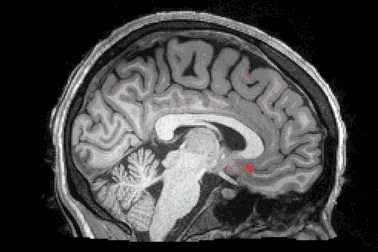

Bộ não sẽ tự “rửa sạch” các chất độc khi chúng ta ngủ theo đúng nghĩa đenMột nghiên cứu mới đây cho thấy, khi chúng ta đi ngủ, bộ não sẽ tiết ra một loại nước “dọn rửa” chảy khắp não bộ và loại bỏ các độc tố phát sinh trong ngày, vốn là nguyên nhân dẫn tới các bệnh thoái hóa thần kinh, điển hình là Alzheimer.